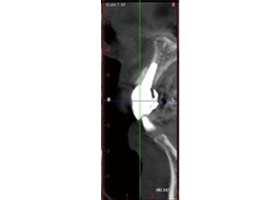

病患植牙前,拍攝3D立體斷層掃描。

當日立即模擬出最適宜的植牙位置。